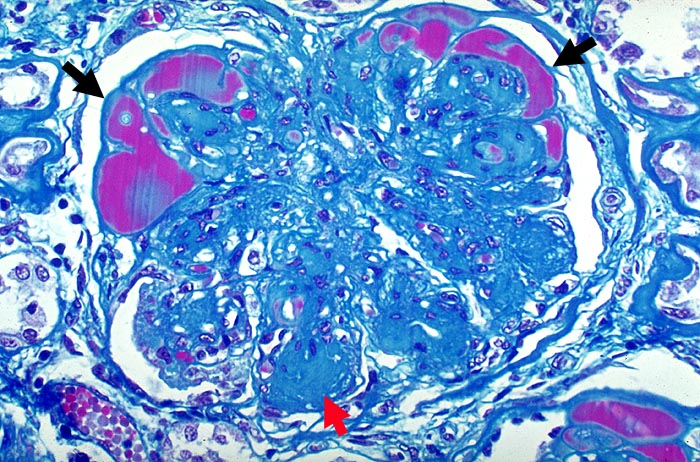

PathoPic – image database / PathoPic ID 1916 - Noduläre diabetische Glomerulosklerose Kimmelstiel-Wilson

Noduläre diabetische Glomerulosklerose Kimmelstiel-Wilson

Die Mesangiumarelae sind ► knotig verdickt. Die Knoten zeigen eine angedeutete Schichtung. Die peripheren Glomerulusschlinge sind hochgradig eingeengt. In Gefässpolnähe werden sie von ► Proteinthromben ausgefüllt (Exsudative Läsion).